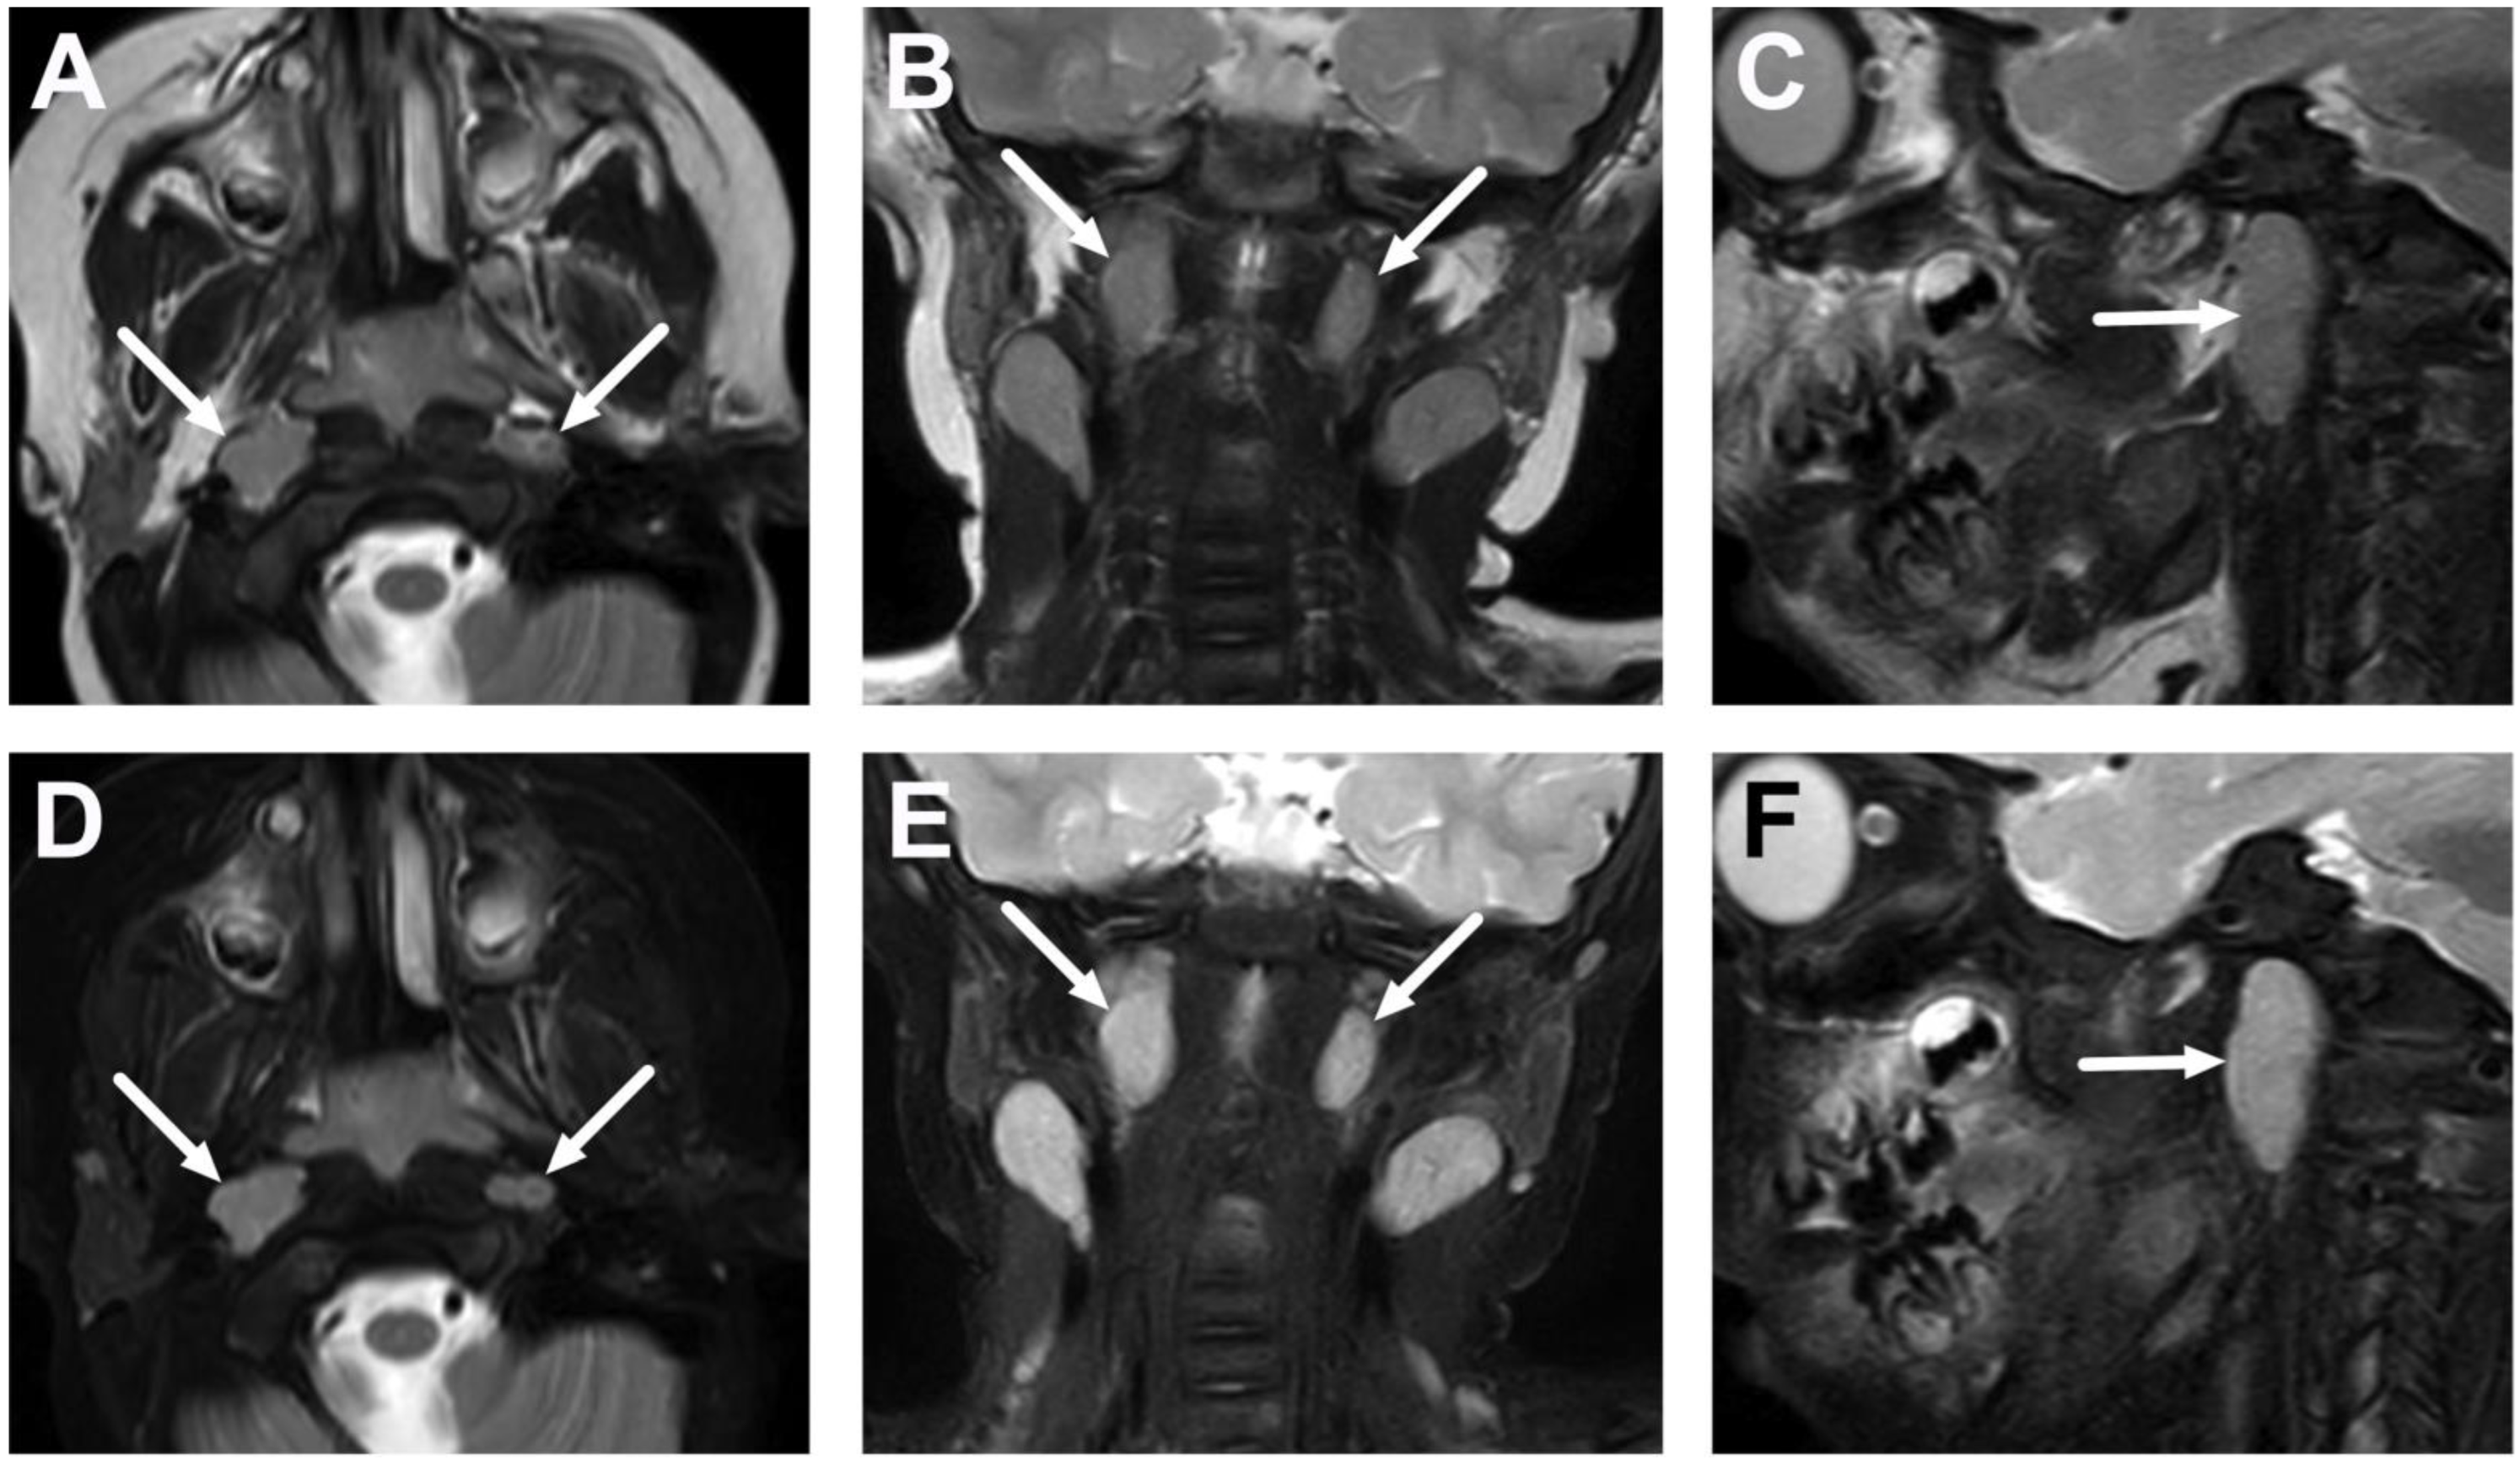

| Abscess | T1 SE T2 Dixon (water) DWI post-contrast T1 Dixon (water) | Non-enhancing collection with low ADC values enclosed in abnormally enhancing soft tissue edema. | Detection of an abscess usually requires operative consideration and exact abscess location, and extensions are useful in operative planning. | Abscesses may have an intermediate T2 signal content; blood products and/or postoperative status may complicate abscess assessment; necrotic lymph nodes may be misinterpreted as suppurative lymphadenitis. |